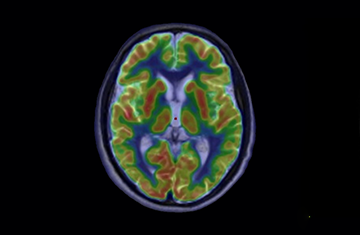

Research areas Cancer diseases Brain diseases PET/MR Special topics Cardiovascular diseases Preclinical research Share on Facebook X Linkedin Email Copy link